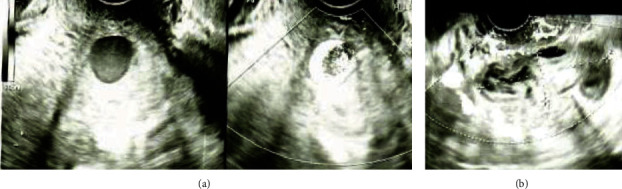

子宫动脉假性动脉瘤(UAP)是妊娠和产后危及生命的并发症。由于没有阴道出血,外生性UAP破裂的早期诊断是困难的。本研究报告了一例31岁的产后妇女,阴道分娩后7天出现腹痛和发烧,无产妇休克症状。超声检查显示外生性UAP破裂伴腹膜出血,经计算机断层扫描证实。介入放射学证实假性动脉瘤位于子宫动脉分叉处,诊断后立即用线圈和正丁-2-氰基丙烯酸酯栓塞。患者症状缓解,栓塞12天后出院。产后8个月,经阴道超声检查未见UAP。即使没有特定的危险因素,如剖宫产或子宫内膜异位症,外生性子宫内膜异位症也可能发生,而且子宫内膜异位症不一定在分娩后立即破裂。产科医生必须保持警惕外源性UAP破裂的可能性,表现为腹痛和产后发烧,而不是不稳定的生命体征。这是首次报道发生在子宫动脉分叉水平的外生性UAP。确定外生性UAP可能发生的部位有助于该病的早期诊断。

A uterine artery pseudoaneurysm (UAP) is a life-threatening complication during pregnancy and postpartum. Early diagnosis of exophytic UAP rupture is difficult due to the absence of vaginal bleeding. This study reports the case of a 31-year-old postpartum woman who presented with abdominal pain and fever seven days after vaginal delivery, without symptoms of maternal shock. Ultrasonography revealed a ruptured exophytic UAP with hemoperitoneum, which was confirmed using computed tomography. Interventional radiology confirmed that the site of the pseudoaneurysm was at the level of the uterine artery bifurcation, and embolization was performed immediately after diagnosis using a coil and n-butyl-2-cyanoacrylate. The patient's symptoms were relieved, and she was discharged 12 days after the embolization. At eight months postpartum, the UAP was not visible on transvaginal ultrasonography. Exophytic UAP can occur even in the absence of specific risk factors such as cesarean section or endometriosis, and the UAP may not necessarily rupture immediately after delivery. Obstetricians must remain aware of the possibility of exophytic UAP rupture manifesting as abdominal pain with postpartum fever, rather than as unstable vital signs. This is the first report of an exophytic UAP that occurred at the level of the uterine artery bifurcation. Identification of the sites where exophytic UAP can occur can aid in the early diagnosis of the condition.